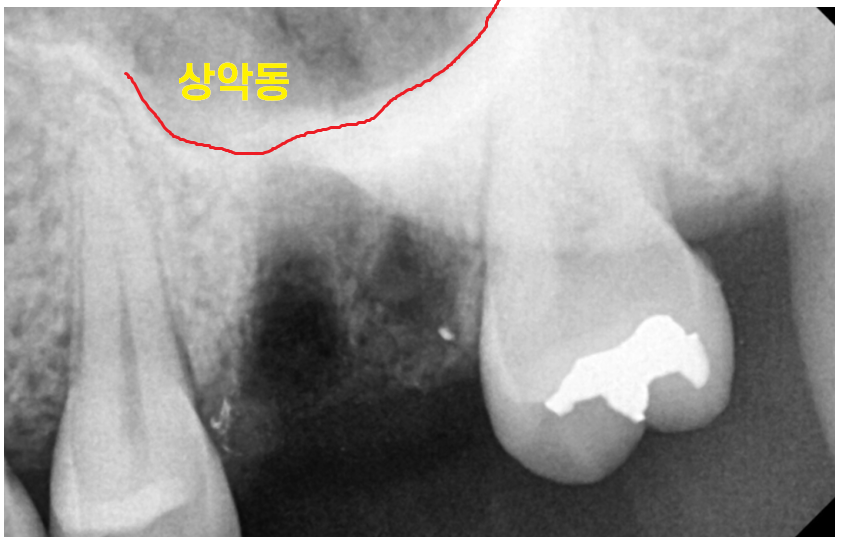

수술 전 치아에 염증이 있었습니다.

염증이 있는 상태에서는

윗니 어금니 발치 중 상악동이 뚫릴 수도 있는데요.

230821

발치 후 사진입니다.

미리 구조물을 x-ray로 확인을 하고 뽑아서 문제없이

안전하게 뽑을 수 있었습니다.